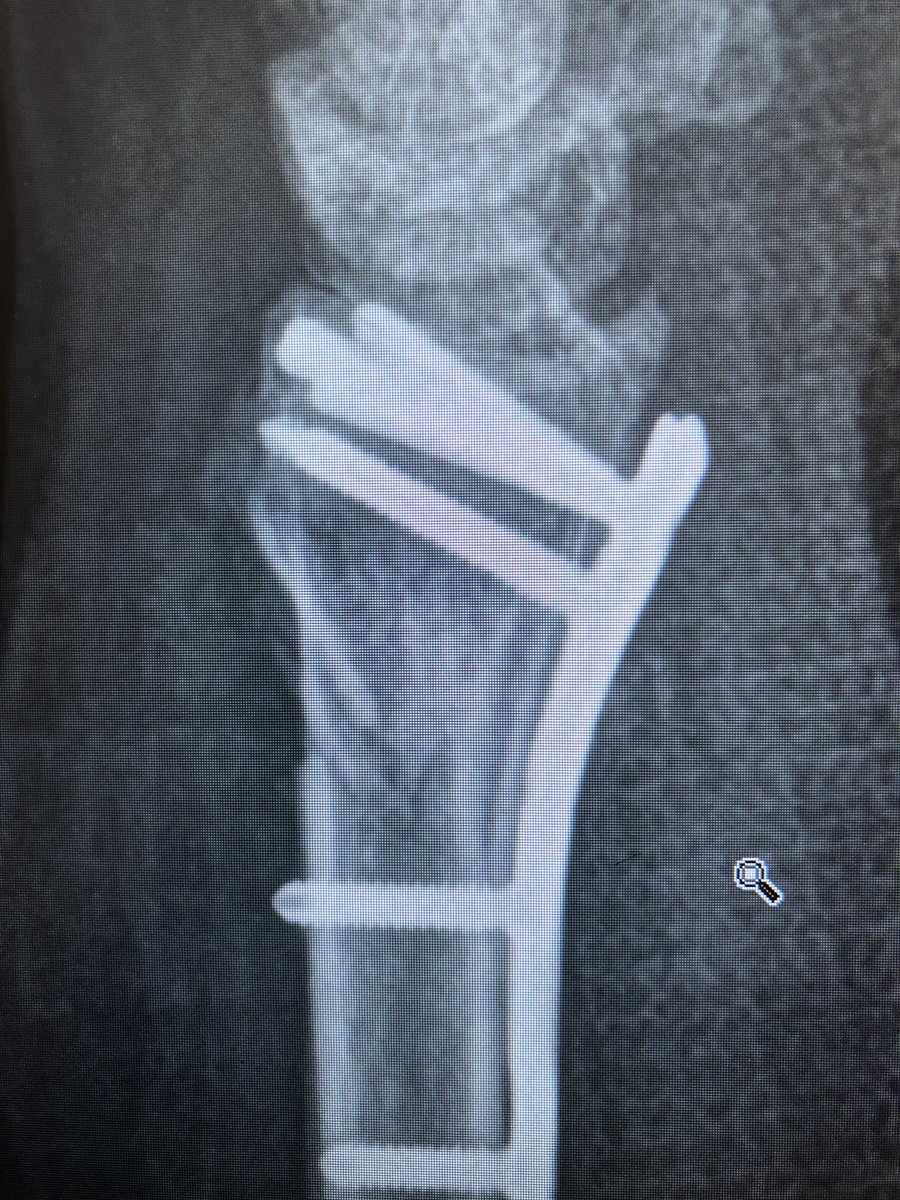

Point 3: the tangential view.

The wrist flexed ‘dorsal tangential view’ or as we locally call it ‘Lleyton Hewitt View’ is increasingly popular (published from our institutes with my colleagues too), but I find the ‘extended tangential’ or ‘DRUJ View’ more informative.

As compared to the dorsal tangential view, this DRUJ view gives better light contrast to view the dorsal rim and also additional information about the DRUJ to make sure there is no screw protrusion into the ulnar notch.